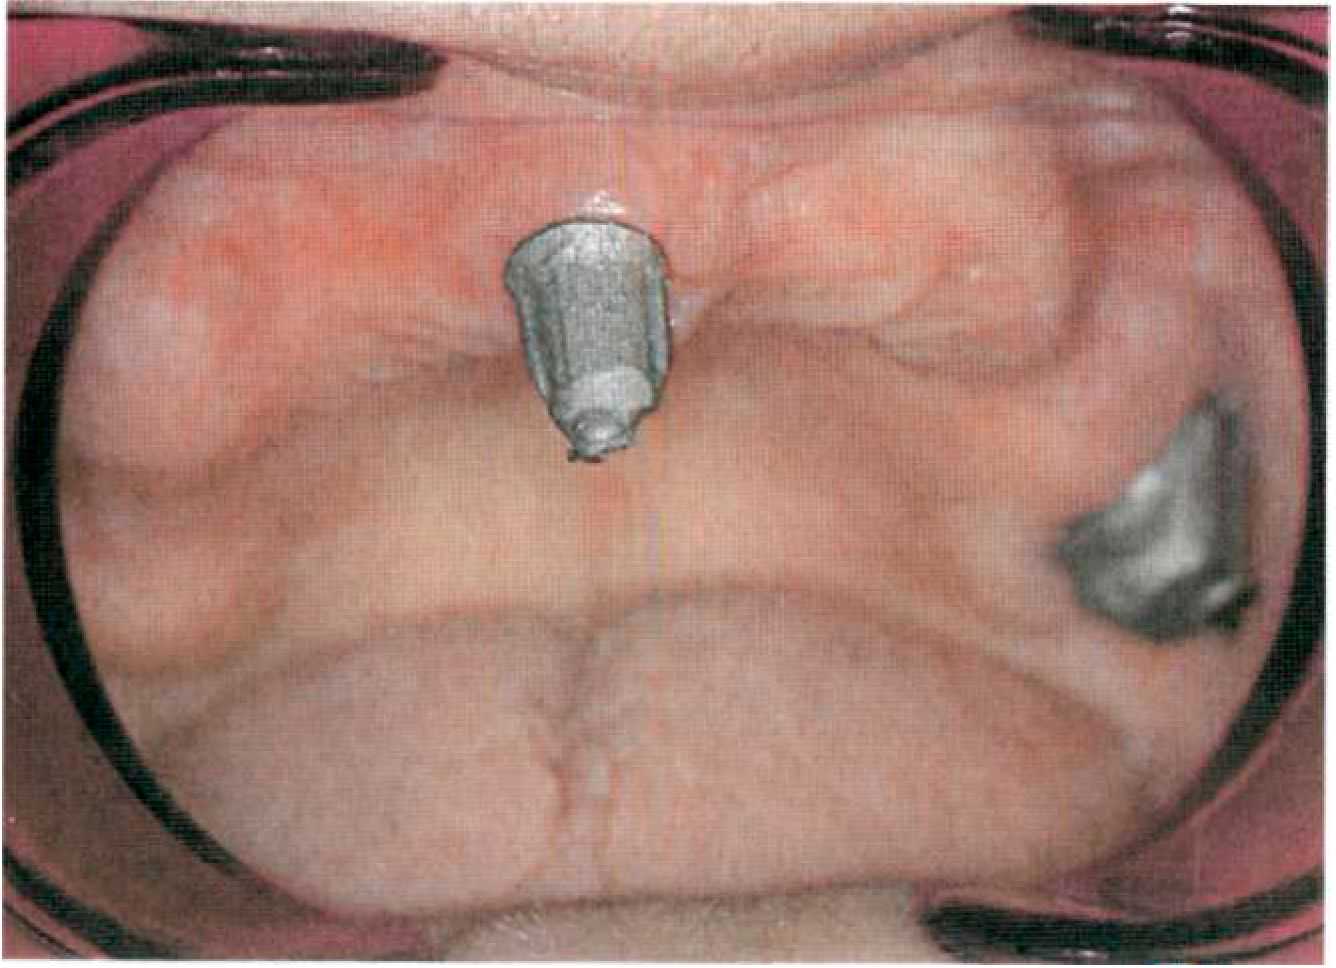

Покрывной протез с телескопическими фиксаторами с фрикционными штифтами Этап 1. После необходимого предварительного обследования, оценки ситуации в полости рта (рис. 127, 128) и санации снимают диагностические оттиски с верхней и нижней челюстей альгинатной массой стандартными ложками, подготавливают диагностические модели из прочного гипса.